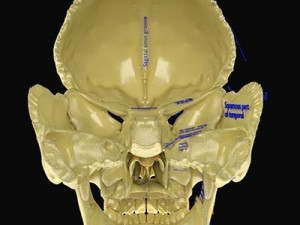

This is a 1:1 scaled model of right breast cut opened in sagittal plane to reveal its internal antomy and histology (schematic). The deeper parts and fascial layers are also depicted to give a very detailed approach to the model. The full layers starting from skin, nipple areola, till intercodtal muscles and ribs are also depicted.